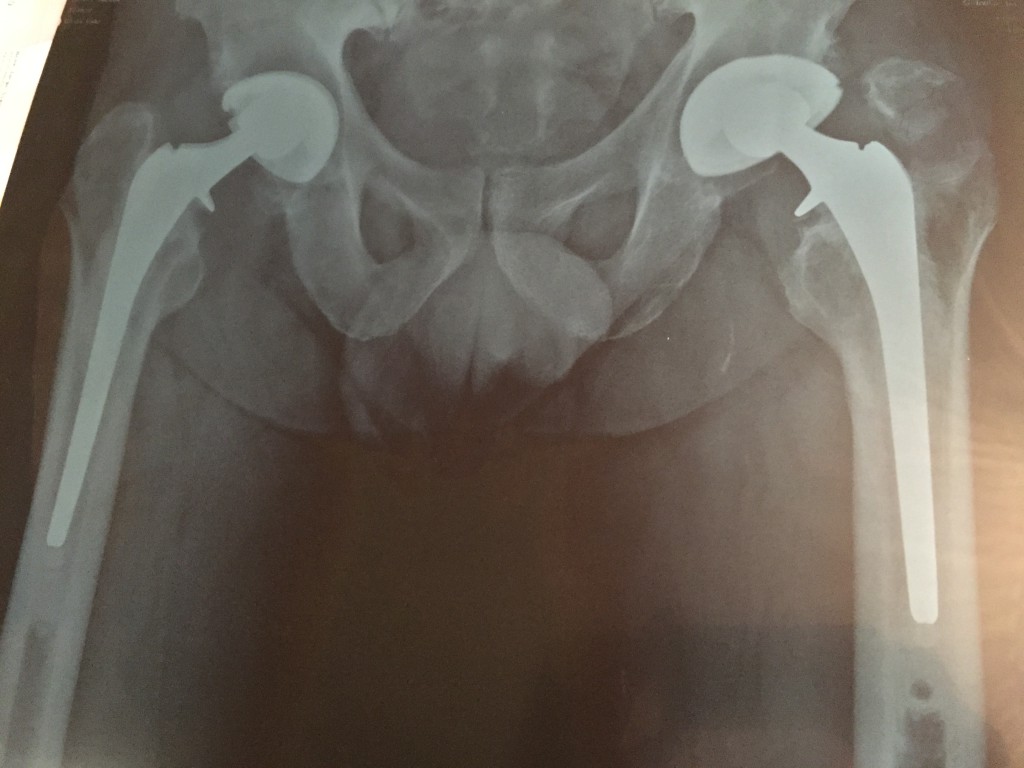

I had a total hip replacement about 15 years ago on my left leg and on my right about 14 years ago. I am very grateful to the amazing Dr. Paul M. Pellicci and the marvelous HSS staff. Soon after my fast recovery, I was back in the game, doing what a like to do best, playing soccer and running about 5K 4 times a week.

And as of my last x-rays done last month, the implants are perfect with no damage at all. They took a quite a beating and pounding all these years. I will be 69 years old on April 3rd.

On my x-ray you will notice that my muscle tore a piece of the bone on my left leg. This happened about six months ago while playing soccer, but I am already running and kicking again.